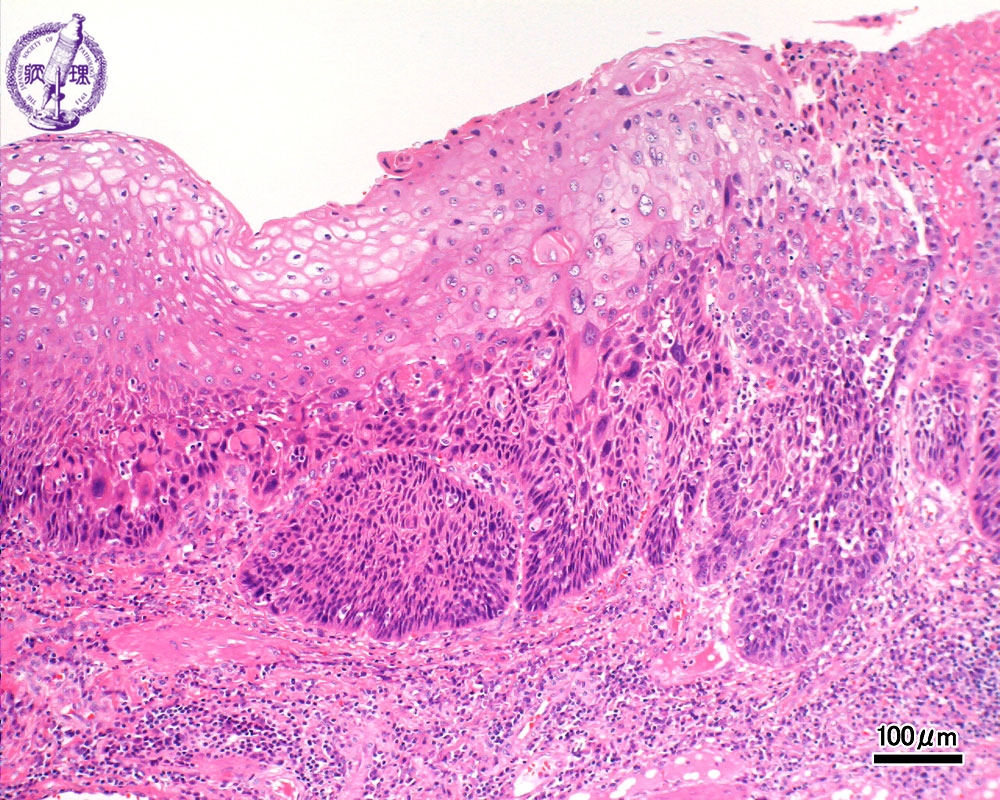

扁平上皮癌は、皮膚の最上層である表皮の上部領域で発生します。基底細胞がんは、表皮の下部領域である基底細胞層で発生します。太陽や紫外線(UV)に長期間さらされると発症する傾向があります。

基底細胞癌および扁平上皮癌は通常、紫外線に長期間曝露された後に発症します。この曝露は、太陽の下で屋外で時間を過ごしたり、日焼けベッドを使用したりすることによって発生する可能性があります。

繰り返し紫外線にさらされると、皮膚を構成する細胞がダメージを受けます。この損傷により、皮膚細胞が制御不能に成長する可能性があります。また、癌の増殖から体を守るのに役立つ腫瘍抑制遺伝子をオフにすることもできます。

医師が基底細胞がんまたは扁平上皮がんの疑いがある場合、皮膚生検を指示することがあります。この手順には、皮膚のサンプルを採取し、検査のために研究室に送ることが含まれます。皮膚サンプルの検査により、皮膚がんの診断を確認できます。